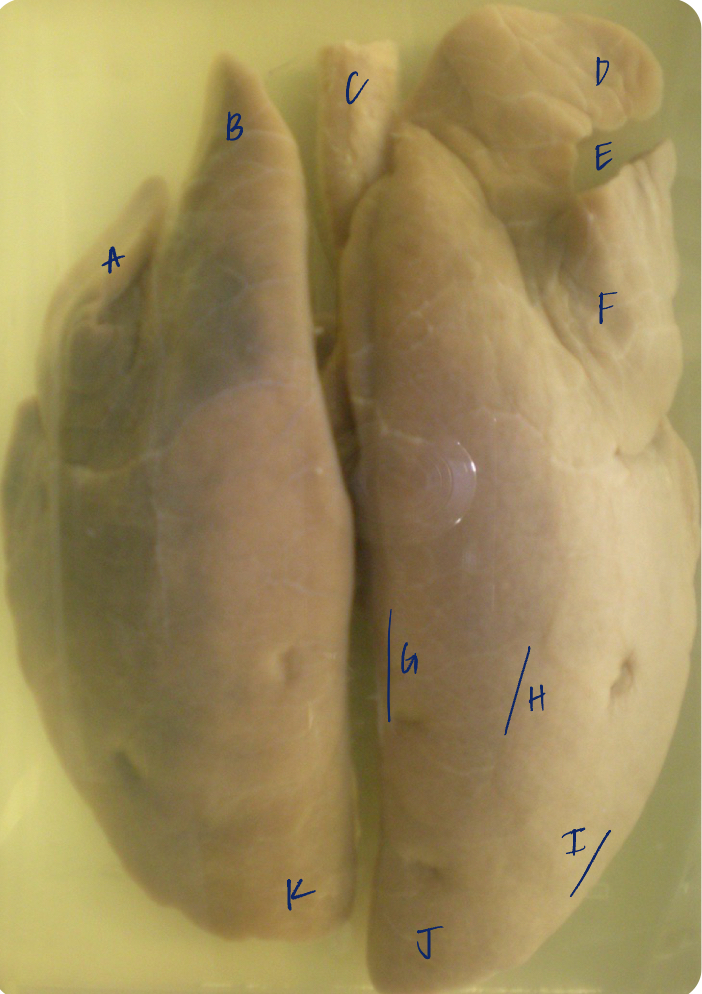

A

(pig lungs, dorsal)

L cranial lobe, caudal segment

B

(pig lungs, dorsal)

L cranial lobe, cranial segment

C

(pig lungs, dorsal)

trachea

D

(pig lungs, dorsal)

R cranial lobe

E

(pig lungs, dorsal)

cardiac notch

F

(pig lungs, dorsal)

middle lobe

G

(pig lungs, dorsal)

dorsal border

H

(pig lungs, dorsal)

costal surface

I

(pig lungs, dorsal)

basal border

J

(pig lungs, dorsal)

R caudal lobe

K

(pig lungs, dorsal)

L caudal lobe

A

(pig lungs, dorsal)

L cranial lobe, caudal segment

B

(pig lungs, dorsal)

L cranial lobe, cranial segment

C

(pig lungs, dorsal)

trachea

D

(pig lungs, dorsal)

R cranial lobe

E

(pig lungs, dorsal)

cardiac notch

F

(pig lungs, dorsal)

middle lobe

G

(pig lungs, dorsal)

dorsal border

H

(pig lungs, dorsal)

costal surface

I

(pig lungs, dorsal)

basal border

J

(pig lungs, dorsal)

R caudal lobe

K

(pig lungs, dorsal)

L caudal lobe